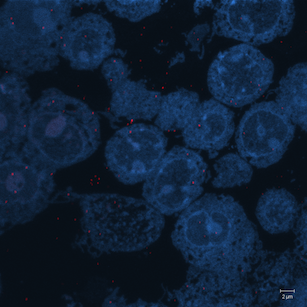

Correlative microscopy is an integration of different microscopy technologies including conventional light, confocal and electron transmission microscopy [6]. Correlative microscopic images usually involve linear or non-linear distortions which are caused by the differences between imaging systems and processing steps. Therefore, the first step of most correlative microscopy based applications is to do registration between two or more microscopic images. An example of correlative microscopic images is presented in Fig. 1.

Refer to caption

(a) Confocal Microscopic Image

(b) Resampling of Boxed Region in Confocal Image

(c) TEM Image

Figure 1: Example of Correlative Microscopy. The goal is to align (b) to (c).

The confocal microscopy images are multichannel color images in our test dataset. The blue channel is based on the blue stain DAPI (a fluorescent stain) which stains the DNA of the cell nucleus and corresponds to dark regions within the nuclei in the TEM. The green channel is based on the stains of the myelin sheats, visible as dark black layers covering the neurons in the TEM images. The red channel is not explicitly stained for and is caused by the auto-fluorescent effect of lipofuscin. The confocal image with RGB channels and its corresponding TEM image are shown in Fig. 5.